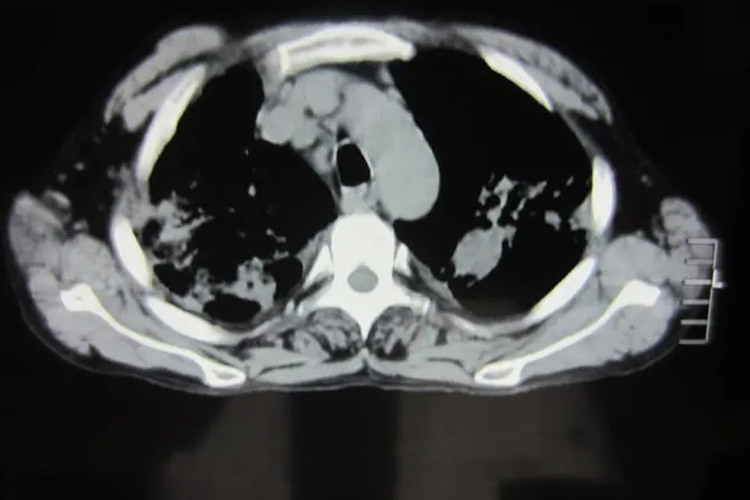

胸壁结核脓肿可通过影像学进行诊断,检查可见胸壁结核脓肿往往呈低回声区,内可见无回声区,血流信号极少。CT检查可见软组织脓肿,且能够明确脓肿的范围。